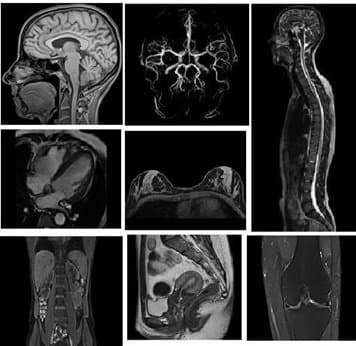

- Nhận được những hình ảnh chất lượng, đa mặt phẳng như mặt phẳng dọc, mặt phẳng ngang, mặt phẳng trán và bất kỳ mặt phẳng nghiêng nào khác.

- Chụp những chuỗi xung định vị tại vùng cần tiến hành thăm khám (ví dụ như chi dưới, chi trên) với ba bình diện.

- Chụp lại xung tĩnh mạch theo như bộ thu tín hiệu mạch tại vùng ngoại biên.

- Chụp lại xung tĩnh mạch khi có tiêm thuốc đối quang từ.

- Góp phần tái tạo được đa bình diện cùng với không gian ba chiều.

- Phát hiện ra những tổn thương trong tĩnh mạch nếu có.

- Hình ảnh sẽ hiển thị rõ toàn bộ những cấu trúc giải phẫu tại vị trí tĩnh mạch đang cần thăm khám.